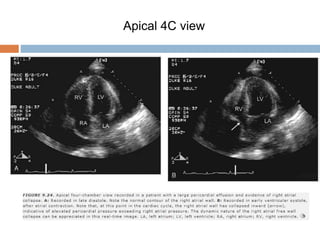

 Right atrial collapse / RA inversion

 Right atrium normally contracts in volume with atrial systole

 In the presence of marked elevation of intrapericardial

pressure, RA wall will remain collapsed throughout atrial

diastole (early ventricular systole)

 Isolated RA inversion occurs during late diastole

 specificity (86%)

 The specificity rose to 100% when the duration of atrial

collapse was > 34% of the cycle length.

Gillam, et. al. 1983. Circulation. 1983, 68: 294-301.

Apical 4C view

 Right ventricular diastolic collapse is a highly sensitive

and specific indicator of Cardiac Tamponade.

 Right atrial collapse although specific for Cardiac

Tamponade was less sensitive for the detection of

Cardiac Tamponade.

 Right heart collapse may not be seen in patients with

pulmonary HTN and Cardiac Tamponade.

Circulation 1984, 70: 966-71.